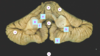

Which structure is the arrow pointing? Thalamus Global pallidus Internal capsule Caudate nucleus Putamen

Which structure is the arrow pointing? Thalamus **Global pallidus** Internal capsule Caudate nucleus Putamen

Which structure is the arrow pointing? **Thalamus** Global pallidus Internal capsule Caudate nucleus Putamen